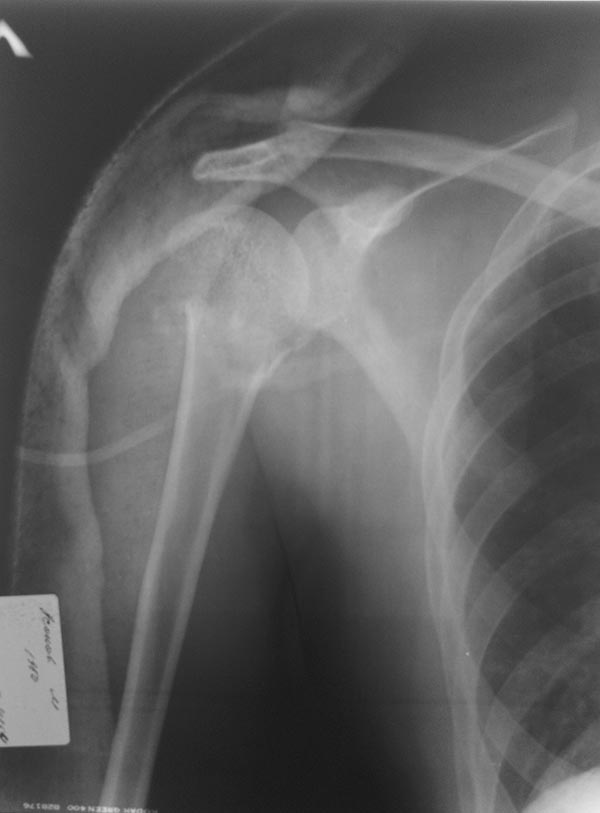

Рентгенограмма левой плечевой кости.